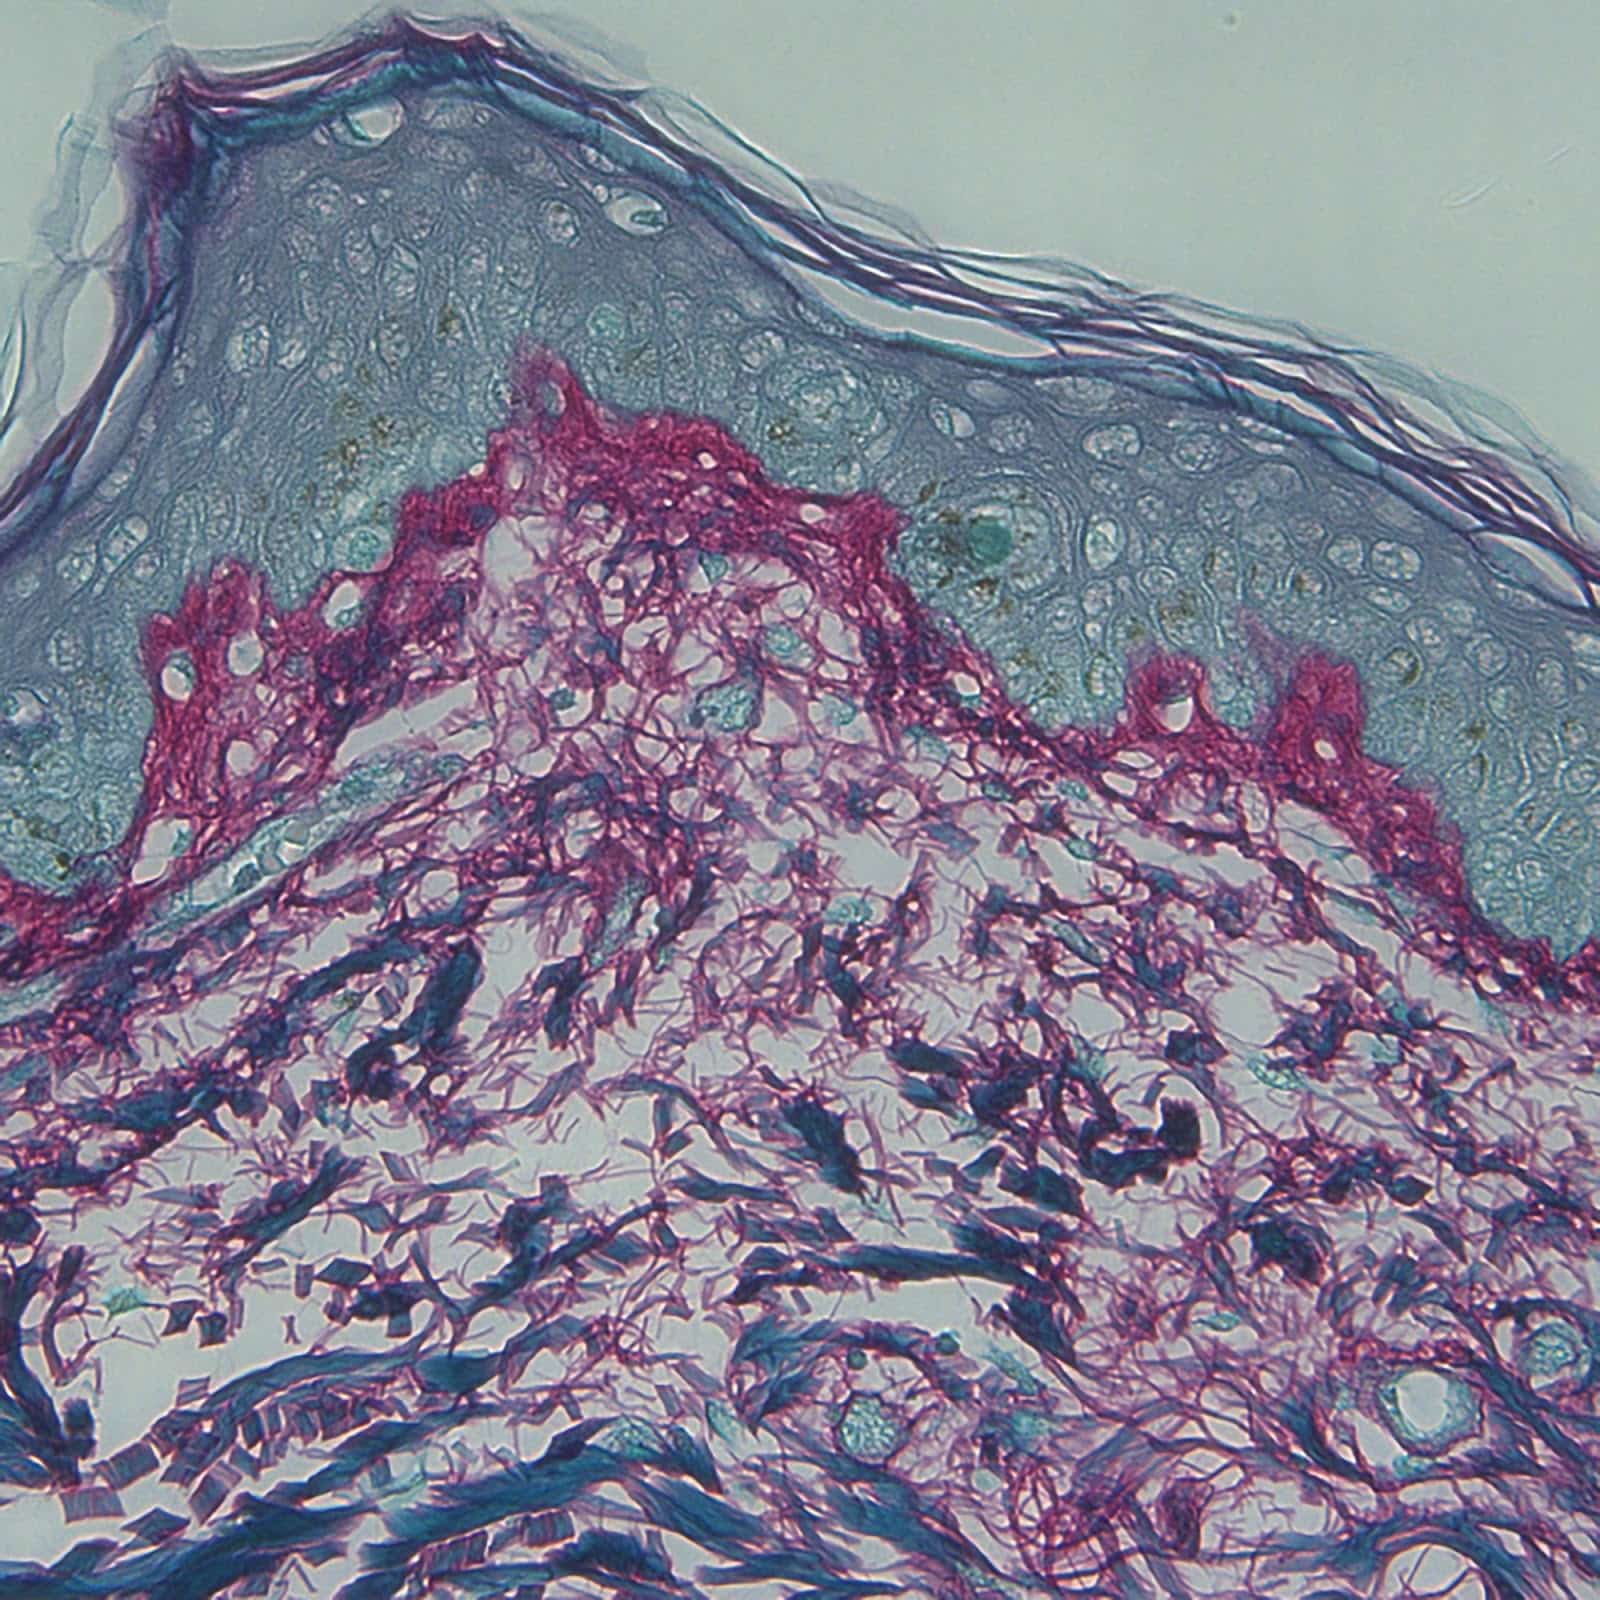

Uno dei principali vantaggi della mesoterapia è la sua capacità di stimolare attivamente la produzione di collagene ed elastina. Queste due proteine strutturali sono fondamentali per mantenere la tonicità e l'elasticità della pelle. Con l'avanzare dell'età, la loro produzione diminuisce, portando alla formazione di rughe e perdita di compattezza. Le microiniezioni di principi attivi favoriscono la neocollagenesi e la neoelastogenesi, contribuendo a ridurre le rughe e a migliorare l'elasticità cutanea, conferendo un aspetto più giovane e riposato.

Viene eseguita utilizzando aghi estremamente sottili, spesso di dimensioni minime (es. 30G o 32G), che rendono le punture quasi impercettibili e minimizzano il disagio. Il complesso di principi attivi viene veicolato direttamente nel derma, lo strato della pelle dove si trovano i fibroblasti (le cellule responsabili della produzione di collagene ed elastina), le fibre di collagene ed elastina, i vasi sanguigni e le terminazioni nervose. L'azione diretta sui tessuti cutanei assicura che gli ingredienti attivi raggiungano le cellule target in modo più efficace rispetto ai trattamenti topici che agiscono solo sulla superficie della pelle.